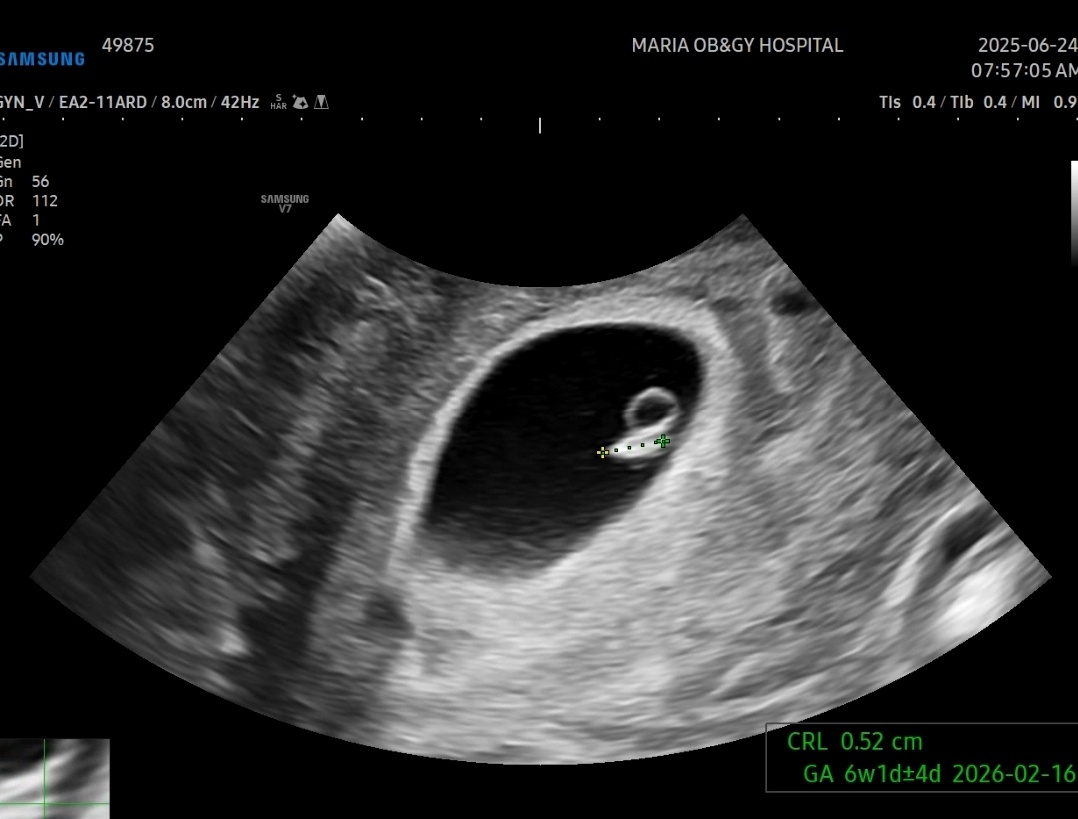

임신 6주 첫 심장소리 확인

아기크기는 0.52cm, 심장소리 118bpm

다음주에 와서 심장소리가 더 빨라졌는지 확인하자고 하셨다